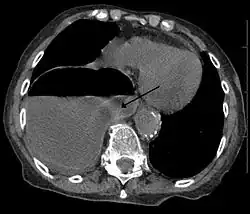

![]() | |

| Diagram of the formation of a ring chromosome | |